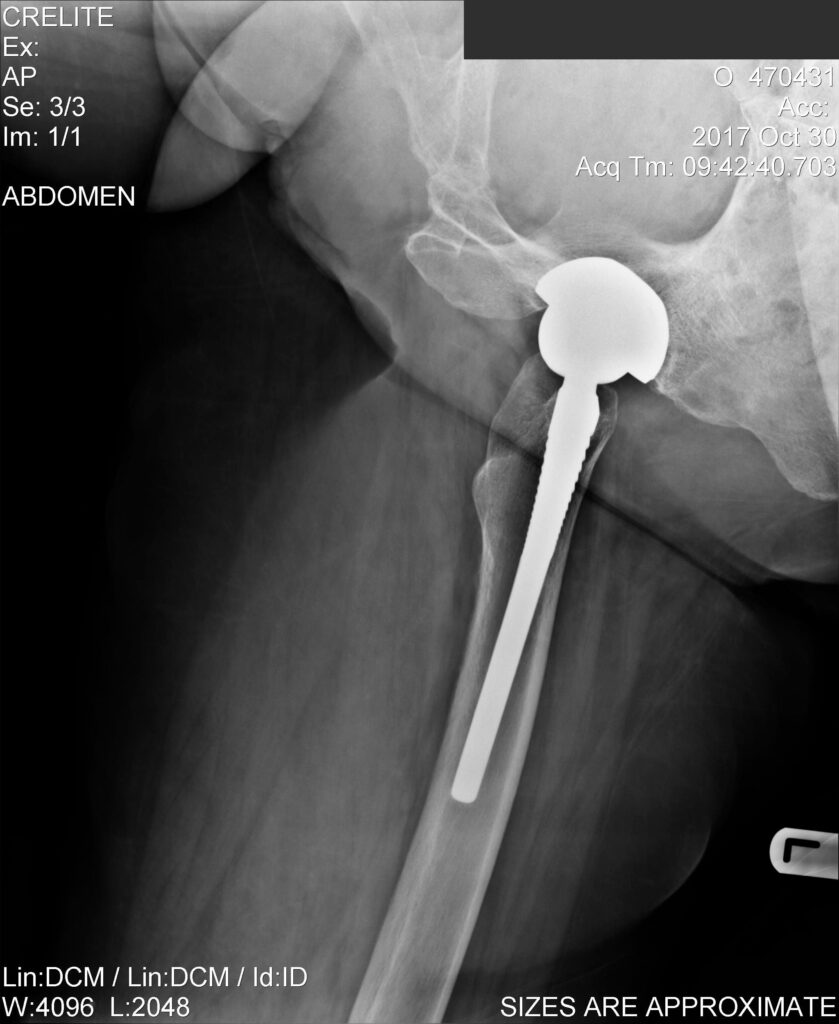

Ακτινογραφίες ασθενή ΜΕΤΑ από επέμβαση αμφοτερόπλευρης αρθροπλαστικής ισχίων που πραγματοποιήθηκε προ 10ετίας